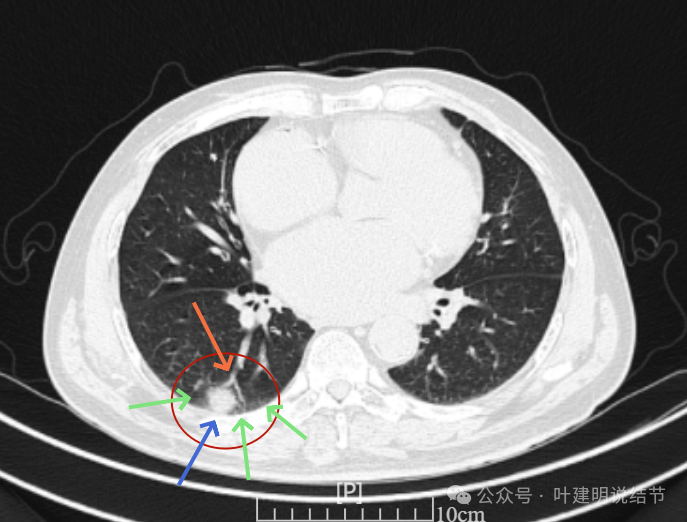

再看2024年6月时的影像:

右下新增病灶,混合密度,整体轮廓较清,瘤肺边界欠清。

有小血管进入,边缘毛糙。

局部有毛刺,但不够锐利;病灶感觉有一层晕似的,邻近胸膜下也有淡磨玻璃影。

实性密度为主,周围少许很淡的磨玻璃影。

边缘不平有毛刺,但不锐利;贴着胸膜但无明显牵拉。局部表面有浅分叶似的,但总体膨胀感不够。

病灶表面不光滑,边上有晕,邻近有淡磨,贴着胸膜无牵拉。

病灶边缘欠清晰,瘤肺边界稍模糊。较宽的基底贴着胸膜。

病灶有血管进入,有浅分叶,实性为主,邻近胸膜有片状淡磨玻璃影,近胸膜无牵拉。但有一定膨胀性。

病灶实性,与血管关系较为密切。

血管走向病灶,但似乎没有被病灶影响,有向内侧的分支甚至没有哪怕一点凹向病灶侧。整体显得偏模糊。

边缘区域杂乱,边糊。